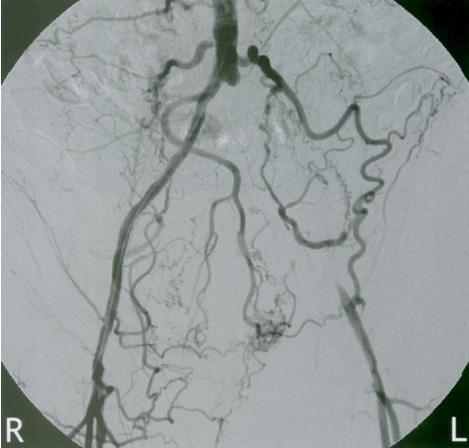

Figura 31. La radiografía de tórax (A) muestra un mediastino ensanchado después de una lesión contusa en el tórax (flechas). Figura 32. El aortograma en proyección anteroposterior (B) muestra un desgarro circunferencial del istmo (flecha). Se observa un pequeño pseudoaneurisma en el sitio de inserción del ligamento arterioso (punta de flecha).